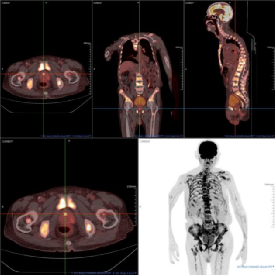

影像学佐证

(附PET/CT图像:前列腺前部正中局灶性高代谢灶SUVmax6.80、全身骨骼多发高代谢灶及纵隔及肺门多发淋巴结异常摄取。)